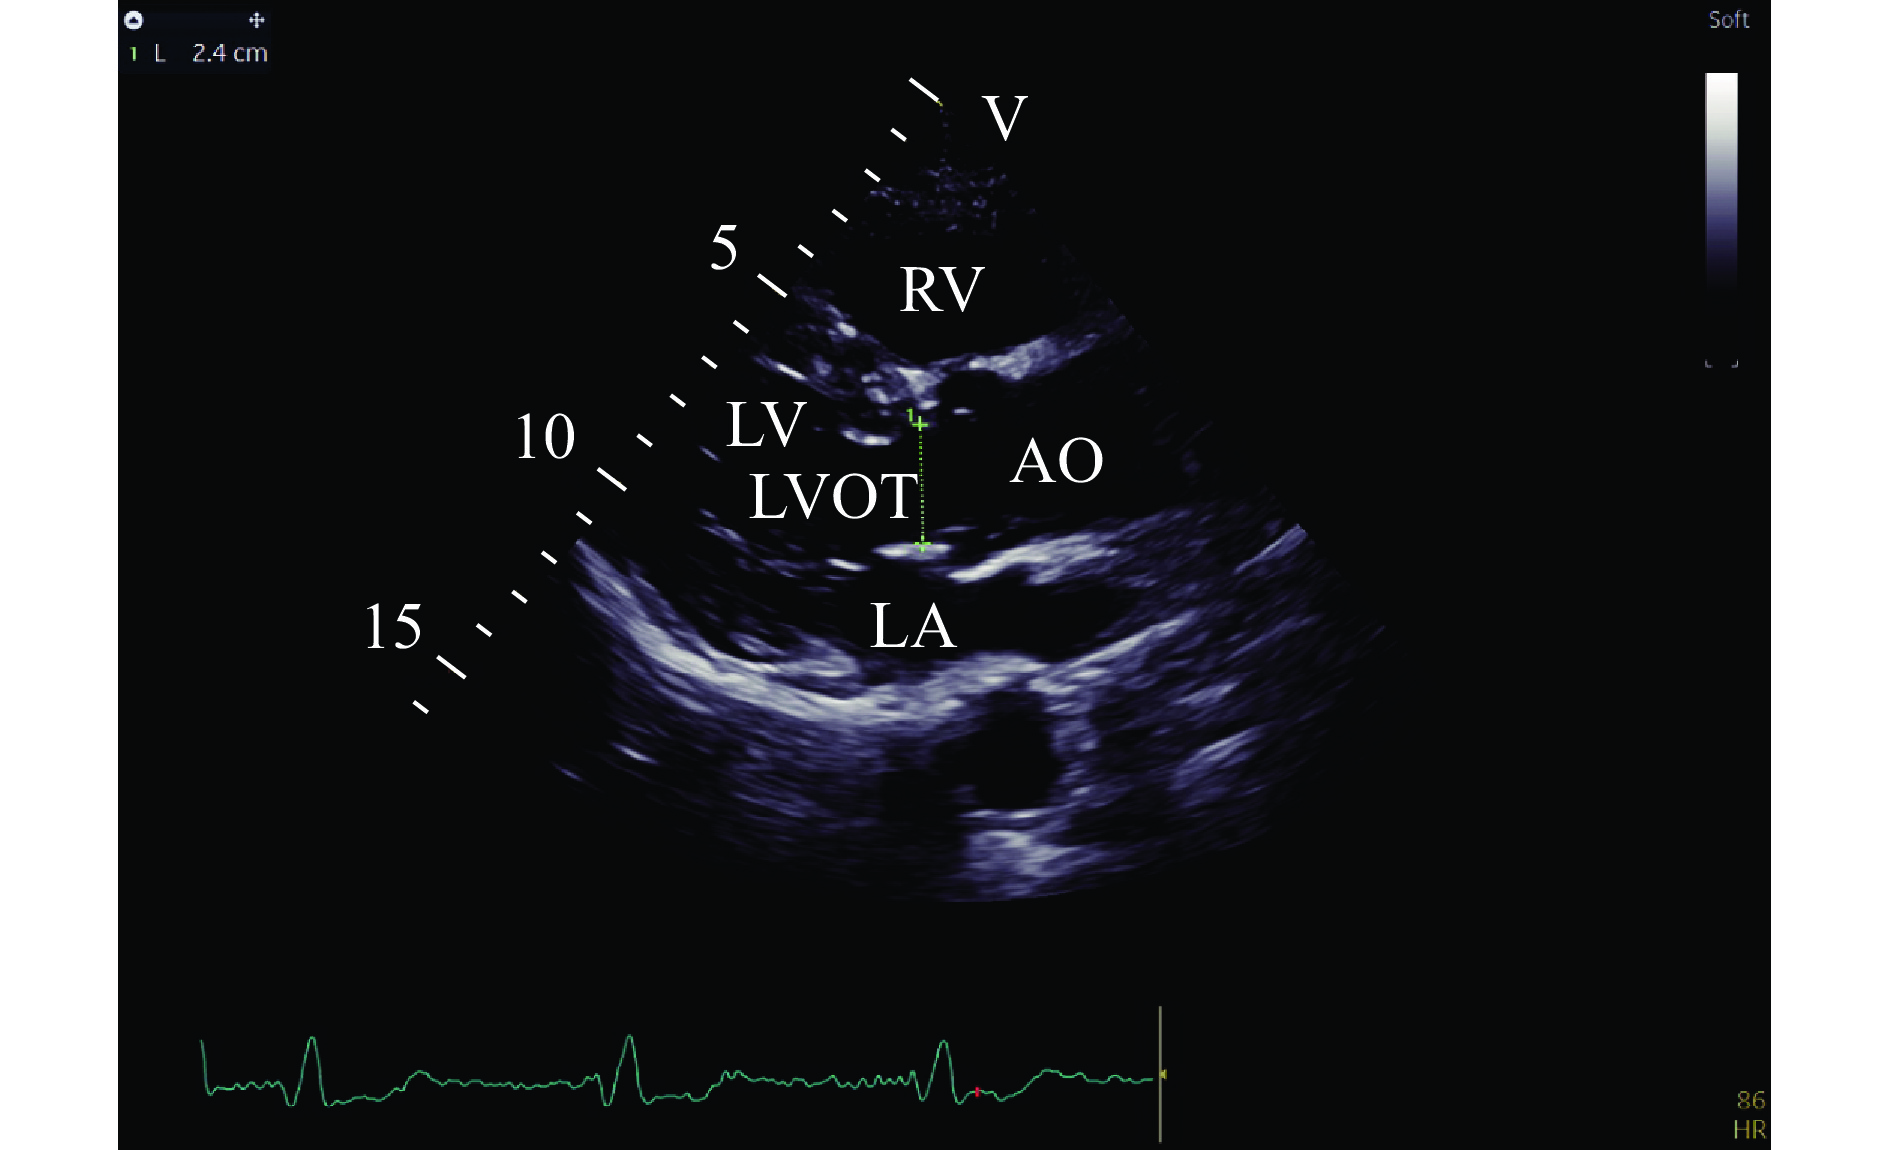

• The current study aimed to compare the effects between remimazolam and propofol on hemodynamic stability during the induction of general anesthesia in elderly patients. We used propofol at a rate of 60 mg/(kg·h) in the propofol group (group P) or remimazolam at a rate of 6 mg/(kg·h) in the remimazolam group (group R) for the induction. A processed electroencephalogram was used to determine whether the induction was successful and when to stop the infusion of the study drug. We measured when patients entered the operating room (T0), when the induction was successful (T1), and when before (T2) and 5 min after successful endotracheal intubation (T3). We found that mean arterial pressure (MAP) was lower at T1–3, compared with T0 in both groups, but higher at T2 in the group R, while ΔMAPT0–T2 and ΔMAPmax were smaller in the group R (ΔMAPT0–T2: the difference between MAP at time point T0 and T2, ΔMAPmax: the difference between MAP at time point T0 and the lowest value from T0 to T3). Cardiac index and stroke volume index did not differ between groups, whereas systemic vascular resistance index was higher at T1–3 in the group R. These findings show that remimazolam, compared with propofol, better maintains hemodynamic stability during the induction, which may be attributed to its ability to better maintain systemic vascular resistance levels.